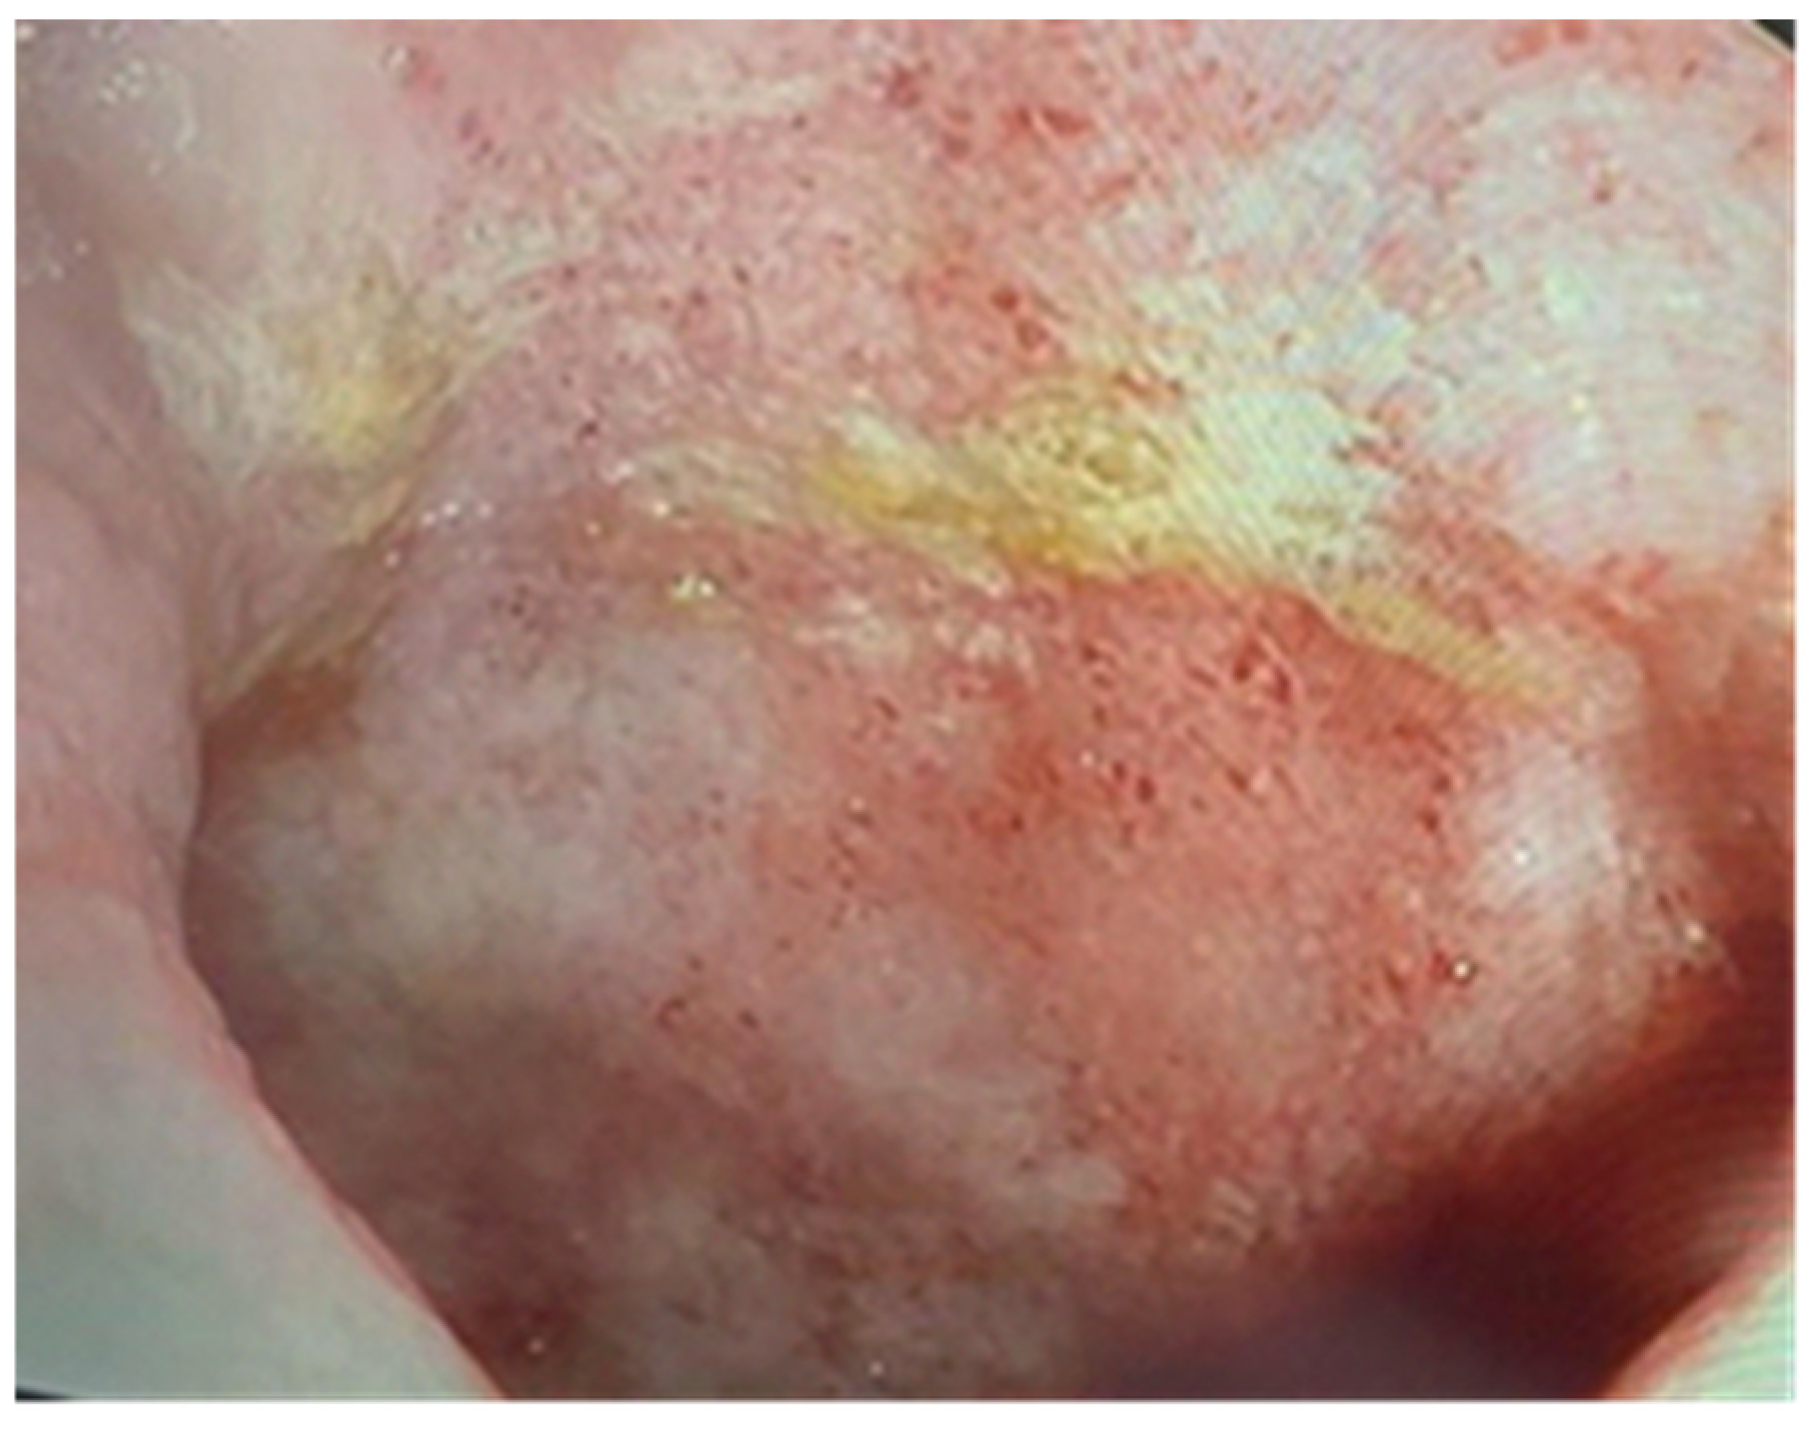

Figure 7.

Endoscopic findings include erosions and a loss of the vascular pattern (atypical for HCMV colitis).

Upon admission, laboratory tests revealed leukopenia, mild hypochromic normocytic anemia, thrombocytopenia, and signs of inflammation, cholestasis, and hepatocellular injury hepatic cytolysis syndrome. To determine the cause of the acute episode, we performed bacterial and mycological stool tests, as well as serological viral marker testing. We found an increase in HCMV IgG levels compared to the value at the initiation of biological therapy: 148 AU/mL and, later, 500 AU/mL. The plasma HCMV DNA was 7320 UI/mL. The HBs Antigen and HCV Antibody tests were negative. The value of anti-adalimumab antibodies was 0.5 (<10 AU/mL). Due to the biochemical changes in the liver, sclerosing cholangitis was initially suspected. However, this was ruled out with the aid of a cholangioMRI and negative pANCA values. Given these findings, HCMV hepatitis was suspected, and an ileocolonoscopy was performed. The endoscopic appearance was not characteristic of HCMV colitis, as there were erosions, ulcerations, a disappearance of the vascular pattern, and mucosal friability, the aspect being circumferential up to the level of the terminal ileum, corresponding to Mayo 8 points (Figure 7). Serial biopsies were collected, especially from the left side. Histopathological examination revealed a destructive pattern with chronic architectural changes and abundant chronic inflammation, including basal plasmocytosis and marked activity with crypt abscesses observed in all biopsy fragments. Rare HCVM viral inclusions were identified on HE staining at the level of the endothelial cells in the capillaries. The presence of the viral inclusions was confirmed by immunohistochemistry (Figure 8 and Figure 9). During hospitalization, the patient was treated with electrolyte solutions, and systemic therapy with intravenous ganciclovir was initiated at 5 mg/kg every 12 h for 3 days, followed by oral valganciglovir at a dose of 900 mg twice a day for 21 days. Additionally, the patient received Mesalazine at a dose of 3 g/day, and hepatoprotective measures were also continued, along with Adalimumab.